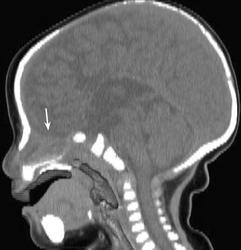

Менингоцеле.

Менингоцеле - этот вид патологических состояний относится к передним мозговым грыжам, обусловленным врожденным дефицитом костной ткани в области дна передней черепной ямки в период эмбрионального развития под влиянием тех или иных внешних (инфекция) и внутренних (генетических) причин, в результате чего происходит задержка смыкания протовертебральных мозговых пластин (пластины Kolliker), что приводит к образованию отверстий в нижней стенке передней черепной ямки, через которые пролабирует вещество головным мозгом. Указанные грыжи получили название передних мозговых грыж. Как уже было отмечено, они образуются путем пролапса сначала мозговых оболочек, образующих мешок, заполненный спиномозговой жидкости, а затем, если отверстие достаточно большое,- и путем выхода в этот мешок и ткани головным мозгом. Обычно этот пролапс происходит через отверстие в области корня носа и glabella. Мозговые грыжи и менингоцеле делятся на два вида:

Патологическая анатомия. Дефект кости в большинстве случаев находится в срединно-сагиттальной плоскости, реже в области затылочного отверстия и чаще всего - в области лобно-носового шва, носоглотки и орбиты. Диаметр дефекта кости при менингоцеле варьирует от 1 до 8 см, а протяженность костного канала, имеющего внутреннее и наружное отверстие, в котором располагается ножка грыжи, бывает до 1 см.

Симптомы и клиническое течение менингоцеле. Признаки менингоцеле делятся на субъективные и объективные. Первые касаются в основном лишь жалоб родителей ребенка или взрослого больного на наличие опухоли в области пролабирования грыжи. Других жалоб, как правило, не возникает. Размеры этой «опухоли» могут варьировать от чечевичного зерна до крупного яблока, имитируя иной раз «второй нос». На ощупь это образование мягкоэластической консистенции, иной раз ножка его уходит в глубь корня носа. Припухлость может пульсировать синхронно с сокращениями сердца, при натуживании (крик или плач ребенка) - увеличиваться, при давлении на нее - уменьшаться. Эти признаки свидетельствуют о связи опухоли с полостью черепа.

Менингоцеле